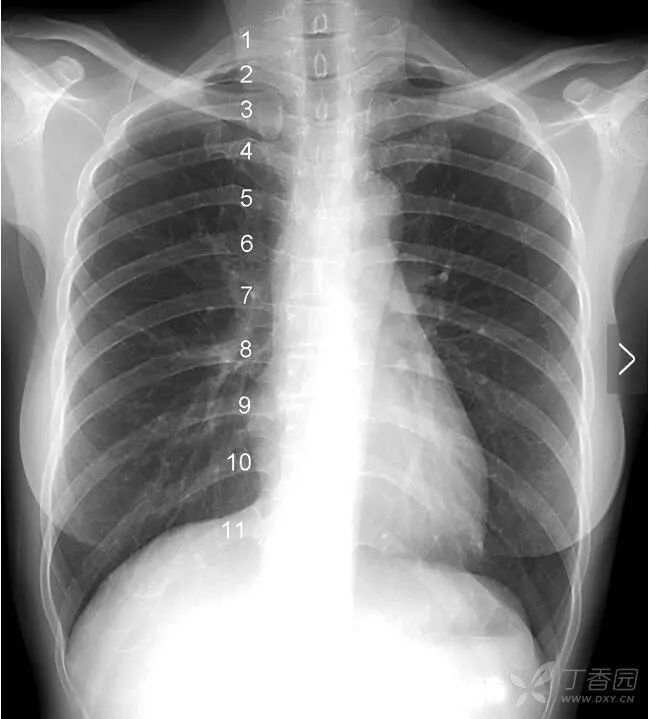

肋 骨 一根肋骨在正位胸片上投影的前后端并不在同一水平,为了便于描述,肋骨被人为的分为后段(后肋)和前段(前肋)两个部分。后段通常是肋骨从胸椎到肺野外缘的投影,走行大致水平或略向外下倾斜。前段从肺野边缘起向内下呈比较大角度的斜向走行,越是接近第11、12肋的肋骨,其前段向下倾斜的角度越大。

图中1~11分别标示第一到第十一后肋。